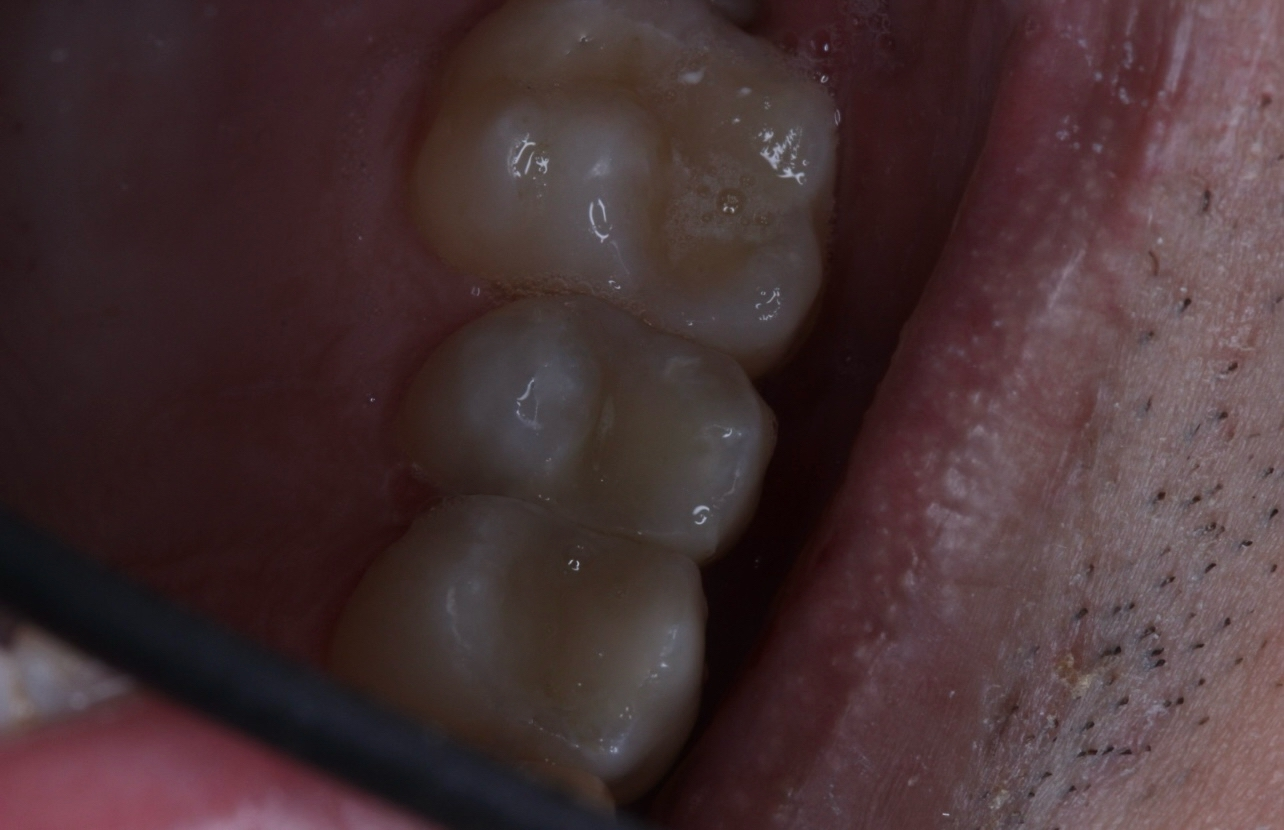

2.jpg 357Кб, 2560x900

2560x900

1.jpg 788Кб, 2560x1429

2560x1429

Двачь помогачь.

Есть одна ебанутая, довела зубы до такого состояния. К доктору идти боятся.

Собственно вопрос, можно ли туда хуй совать что можно сделать в домашних условиях. Она ведёт эталонный нищенский хиканский образ жизни, возможет ли это быть результат диеты или "плохой" воды? Зубы чистить не умеет, но не думаю что если научится, это сильно изменит ситуацию.